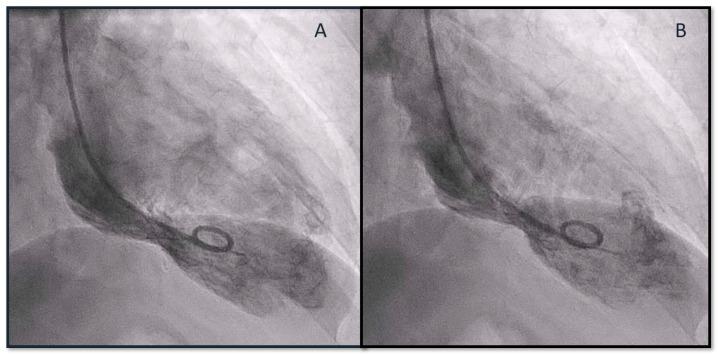

曲妥珠单抗和帕妥珠单抗治疗HER2阳性转移性乳腺癌期间的应激性心肌病综合征

Takotsubo Syndrome during Pertuzumab and Trastuzumab Therapy for HER2-Positive Metastatic Breast Cancer.

Pertuzumab and trastuzumab have been shown to improve the outcomes of patients with metastatic breast cancer, with a rate of left ventricular dysfunction of approximately 6%. We report the case of a postmenopausal woman who presented with Takotsubo syndrome during maintenance therapy with pertuzumab and trastuzumab, in association with fulvestrant (an anti-estrogen) and denosumab. After normalization of cardiac function, therapy with pertuzumab and trastuzumab was resumed in the absence of new cardiac toxicity. We report the first clinical case of Takotsubo syndrome during double anti-HER2 blockade in association with an antiestrogen. Furthermore, we show how anti-HER2 therapy can be safely resumed after the detection of Takotsubo syndrome.

摘要

帕妥珠单抗和曲妥珠单抗已被证明可改善转移性乳腺癌患者的预后,左心室功能障碍发生率约为6%。我们报告了一例绝经后女性病例,该患者在接受帕妥珠单抗、曲妥珠单抗联合氟维司群(一种抗雌激素药物)和地诺单抗维持治疗期间出现了Takotsubo综合征。在心脏功能恢复正常后,在没有新的心脏毒性的情况下恢复了帕妥珠单抗和曲妥珠单抗治疗。我们报告了首例在双重抗HER2阻断联合抗雌激素治疗期间发生Takotsubo综合征的临床病例。此外,我们展示了在检测到Takotsubo综合征后如何安全地恢复抗HER2治疗。